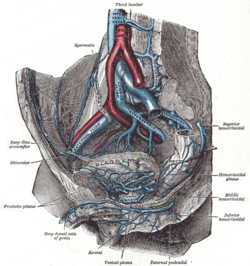

Testicular artery of a bull (steer). The veins of the right half of the male pelvis.

The veins of the right half of the male pelvis. Spermatic veins.